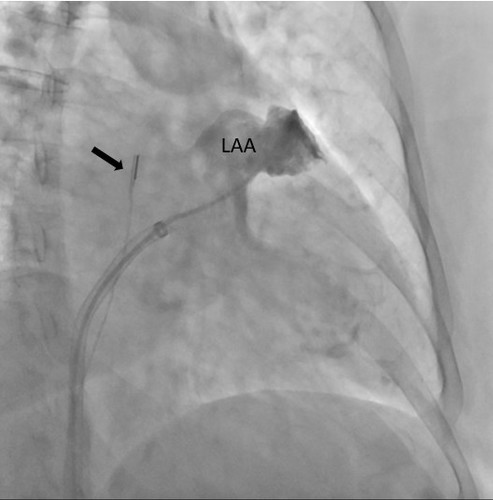

Specjaliści z Pracowni Kardiologii Inwazyjnej I Kliniki Kardiologii UCK przeprowadzili 3 zabiegi zamknięcia uszka lewego przedsionka (ang. LAAO – left atrial appendage occlusion) z wykorzystaniem systemu echokardiografii wewnątrzsercowej (ang. ICE – intracardiac echocardiography).

– U części pacjentów kwalifikowanych do LAAO ryzyko związane z wykorzystaniem obrazowania metodą TEE jest zbyt wysokie ze względu na poważne zmiany chorobowe przełyku. To dotychczas uniemożliwiało wykonanie zabiegu. Obrazowanie metodą ICE pozwala na bezpieczne wykonanie zabiegu zamknięcia uszka lewego przedsionka również w tej grupie chorych, ponieważ specjalną sondę ultrasonograficzną wprowadza się nie do przełyku, lecz przez układ żylny pacjenta, bezpośrednio do jam serca – mówi dr Dariusz Ciećwierz, koordynator Pracowni Kardiologii Inwazyjnej I Kliniki Kardiologii UCK z I Katedry i Kliniki Kardiologii GUMed. – Dodatkową korzyścią tego rozwiązania jest większy komfort pacjenta w trakcie zabiegu, dzięki czemu można uniknąć sedacji czy znieczulenia ogólnego.

Szczególną grupą pacjentów kwalifikowanych do zabiegu zamknięcia uszka lewego przedsionka są chorzy z marskością wątroby, u których wytworzyły się żylaki przełyku.

– Mogą one powodować ciężkie krwawienia, co sprawia, że u części takich pacjentów nie ma możliwości leczenia przeciwzakrzepowego i proponuje się zabieg LAAO. Z drugiej strony wprowadzenie sondy ultrasonograficznej do zmienionego chorobowo przełyku samo w sobie wiąże się z wysokim ryzykiem wystąpienia krwawienia z żylaków. U takich chorych mamy obecnie możliwość wykonania zabiegu z zastosowaniem obrazowania metodą ICE – tłumaczy prof. Marcin Fijałkowski, koordynator Oddziału Chorób Strukturalnych I Kliniki Kardiologii UCK z I Katedry i Kliniki Kardiologii GUMed.